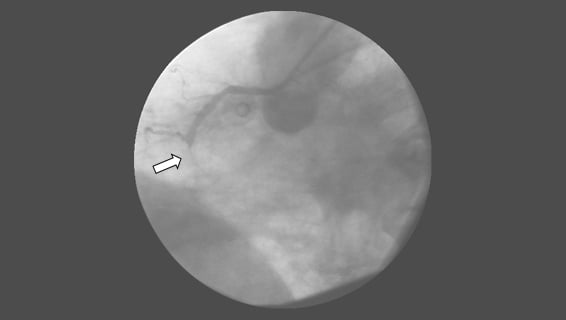

• If the patient arrives early to open the blocked coronary arteries, first emergency coronary angioplasty (balloon) is performed and after angioplasty, a steel cage called a stent is placed to keep the coronary artery open.